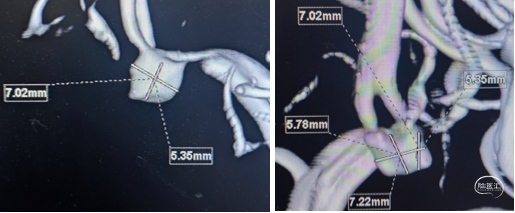

WEB选择:理想SL9x3(没有),选择SL8x4

直接测量:7.4x3.92mm

3D测量:7.22x5.35mm

对比测量:8.9x4.8mm(偏大10%)